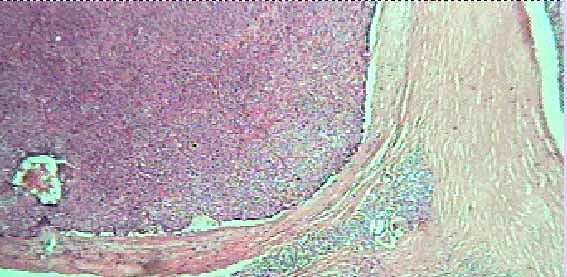

Figura 2

Fig. 2.- Aspecto microscópico del adenoma (Caso 7) de celulas principales, patrón sólido. Notese el anillo de tejido paratiroideo normal en el tejido fibroso capsular. HE x 100